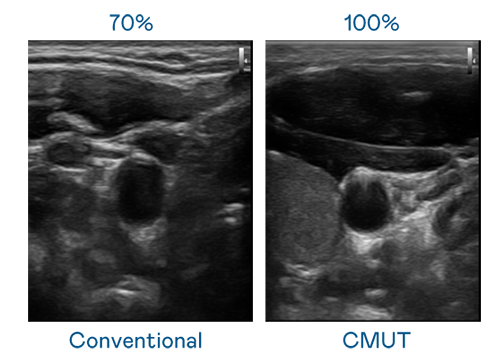

CMUT 技术是一种用电容式微机电元件来产生超音波讯号的技术。与传统 PZT 压电式技术相比,CMUT 频宽增加 30%,更宽频的超音波讯号让影像解析度大幅提升,是实现高影像品质医疗超音波扫描、促进精准医疗发展的关键技术。

大频宽带来超清晰影像

超音波影像的解析度高低,首先取决于探头能发出的讯号频宽。旺财28 CMUT 可提供高清晰的超音波讯号,提供高频宽、高灵敏度、影像纹理细节更高的超音波影像,协助医护人员缩短影像判读时间及利用精准的医疗影像进行诊断。